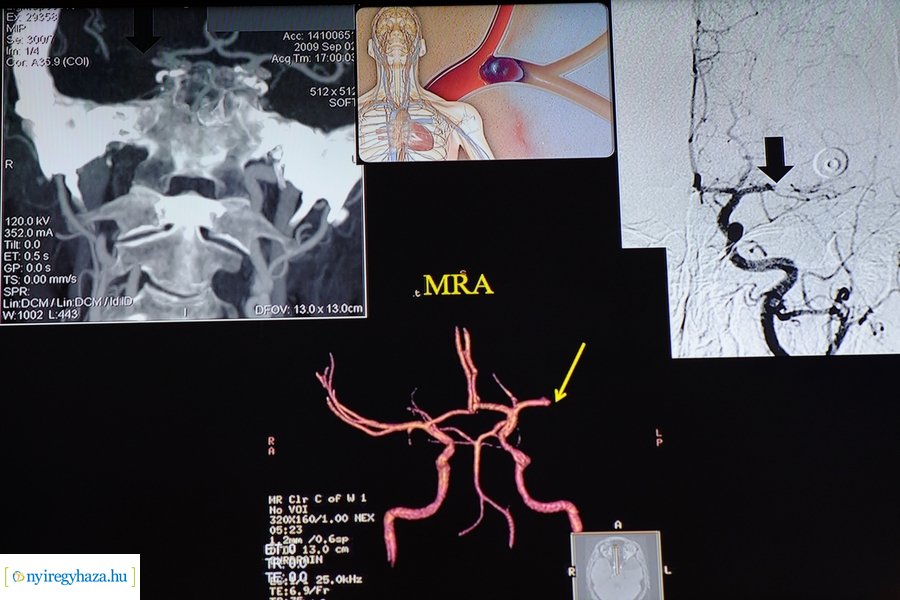

A Neurológiai Osztály múltján kívül a megemlékezésen tudományos előadásokat is hallhattak a résztvevők, dr. Varannai Lajos „A mindennapok ma: kezelési lehetőségek előrehaladott Parkinson-kórban” címmel, prof. dr. Oláh László pedig „Újdonságok az ischaemiás stroke terápiájában” címmel tartott előadást.